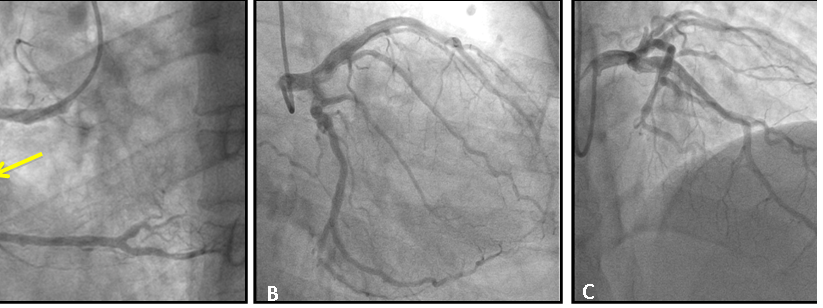

Figure 5 (A) right coronary angiography in left oblique projection demonstrating total occlusion of the non-dominant right coronary in its proximal portion (arrow); (B) left coronary angiography in direct cranial projection demonstrating mild obstructive lesion in diagonal branch; (C) left coronary angiography in right obliquous projection demonstrating dominant circumflex branch with mild obstructive lesion in its proximal portion.